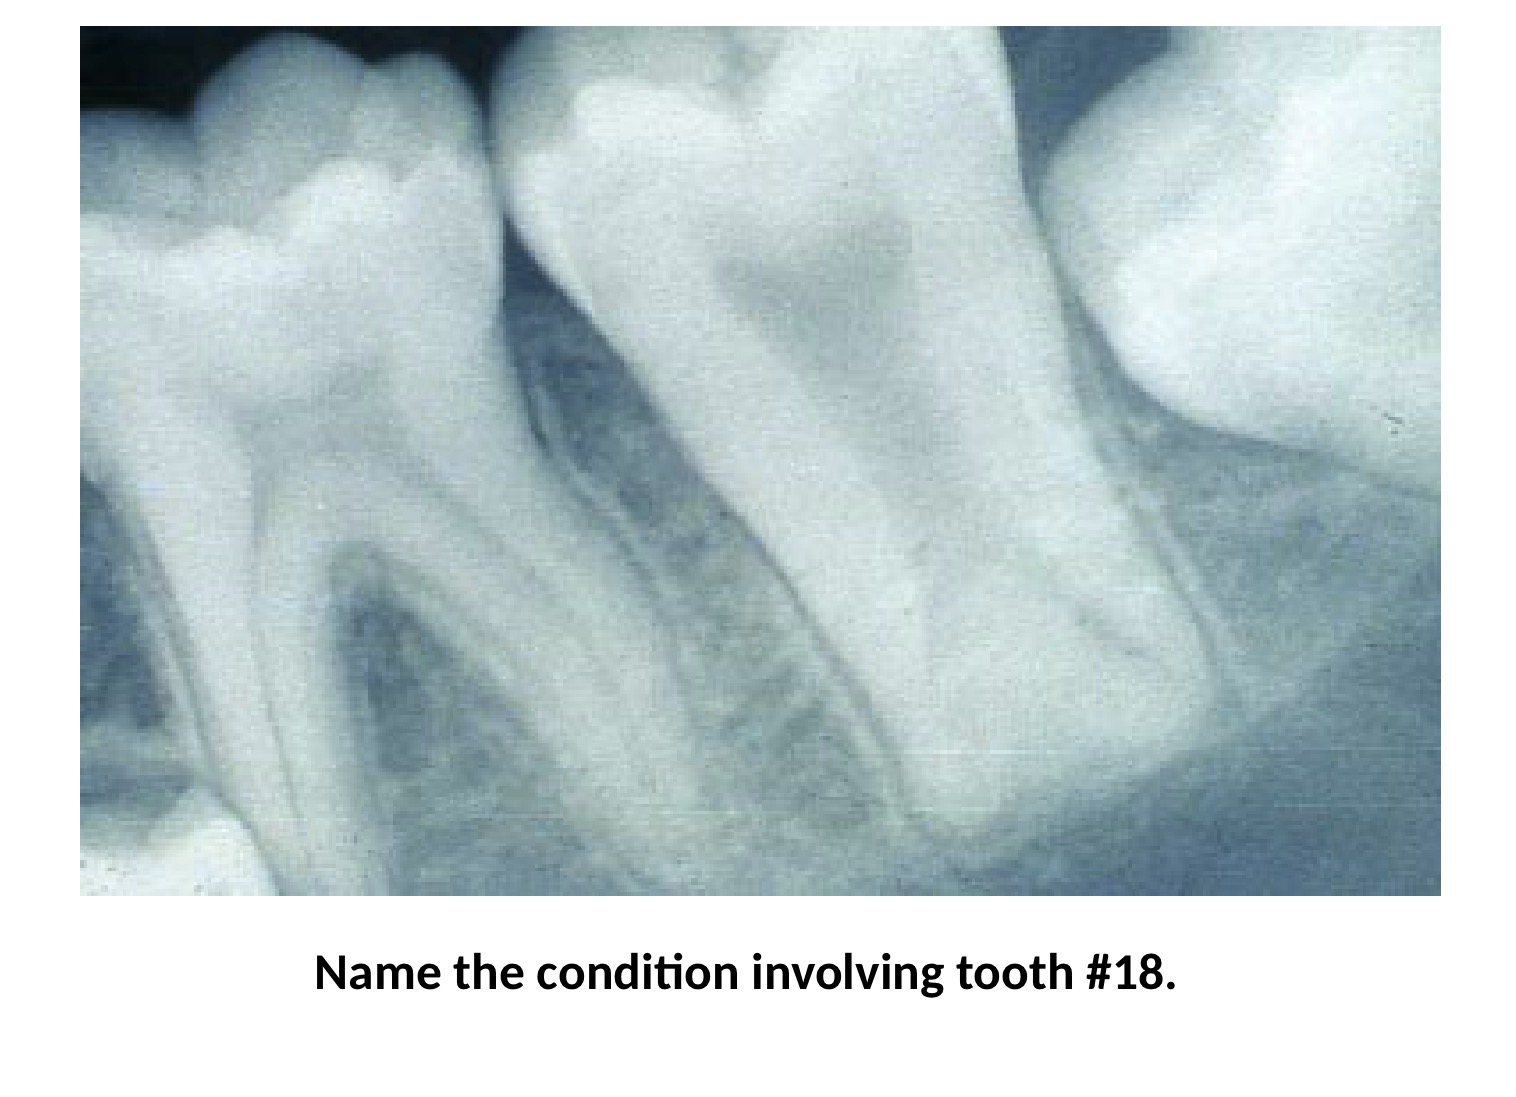

Dilaceration